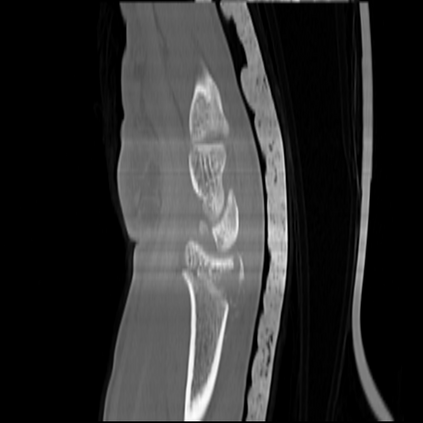

CT reconstruction provides radiologists with images for diagnosis and treatment, yet current deep learning methods are typically limited to specific anatomies and datasets, hindering generalization ability to unseen anatomies and lesions. To address this, we introduce the Multi-Organ medical image REconstruction (MORE) dataset, comprising CT scans across 9 diverse anatomies with 15 lesion types. This dataset serves two key purposes: (1) enabling robust training of deep learning models on extensive, heterogeneous data, and (2) facilitating rigorous evaluation of model generalization for CT reconstruction. We further establish a strong baseline solution that outperforms prior approaches under these challenging conditions. Our results demonstrate that: (1) a comprehensive dataset helps improve the generalization capability of models, and (2) optimization-based methods offer enhanced robustness for unseen anatomies. The MORE dataset is freely accessible under CC-BY-NC 4.0 at our project page https://more-med.github.io/